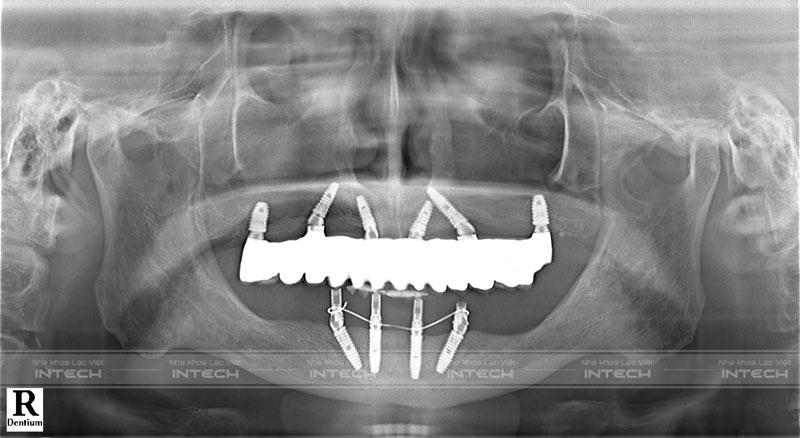

• Trồng răng Implant All On 6 hàm trên và All On 4 hàm dưới

Chia sẻ cảm nhận về quá trình trồng răng Implant tại Nha khoa Lạc Việt Intech, chú bình cho biết: “Trước khi trồng răng, bác sĩ đã cho tôi xem phác đồ điều trị và chỉ rõ vị trí đặt trụ Implant gồm 6 vị trí hàm trên và 4 vị trí hàm dưới thông qua phần mềm máy tính. Trải nghiệm rồi mới thấy trang thiết bị tại Nha khoa Lạc Việt Intech rất hiện đại và đầy đủ. Phòng khám thì rất sạch sẽ với không gian rộng rãi, chia từng khu điều trị riêng biệt.”

Hình ảnh phim chụp X-quang sau cấy ghép Implant của chú BìnhHình ảnh phim chụp X-quang sau cấy ghép Implant của chú Bình